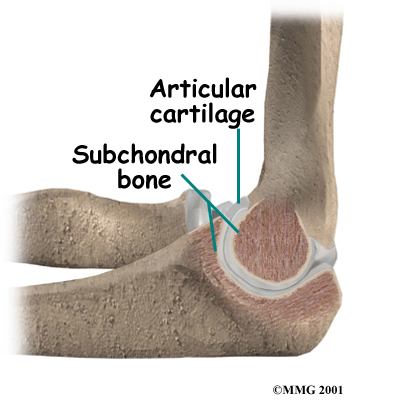

Articular cartilage is the material that covers the ends of the bones of any joint. Articular cartilage can be up to one-quarter of an inch thick in the large, weight-bearing joints. It is a bit thinner in joints such as the elbow, which don't support weight. Articular cartilage is white, shiny, slippery, and has a rubbery consistency.

The function of articular cartilage is to absorb shock and provide an extremely smooth surface to make motion easier. It allows joint surfaces to slide against one another without causing any damage. We have articular cartilage essentially everywhere that two bony surfaces move against one another, or articulate. In the elbow, articular cartilage covers the end of the humerus, the end of the radius, and the end of the ulna.